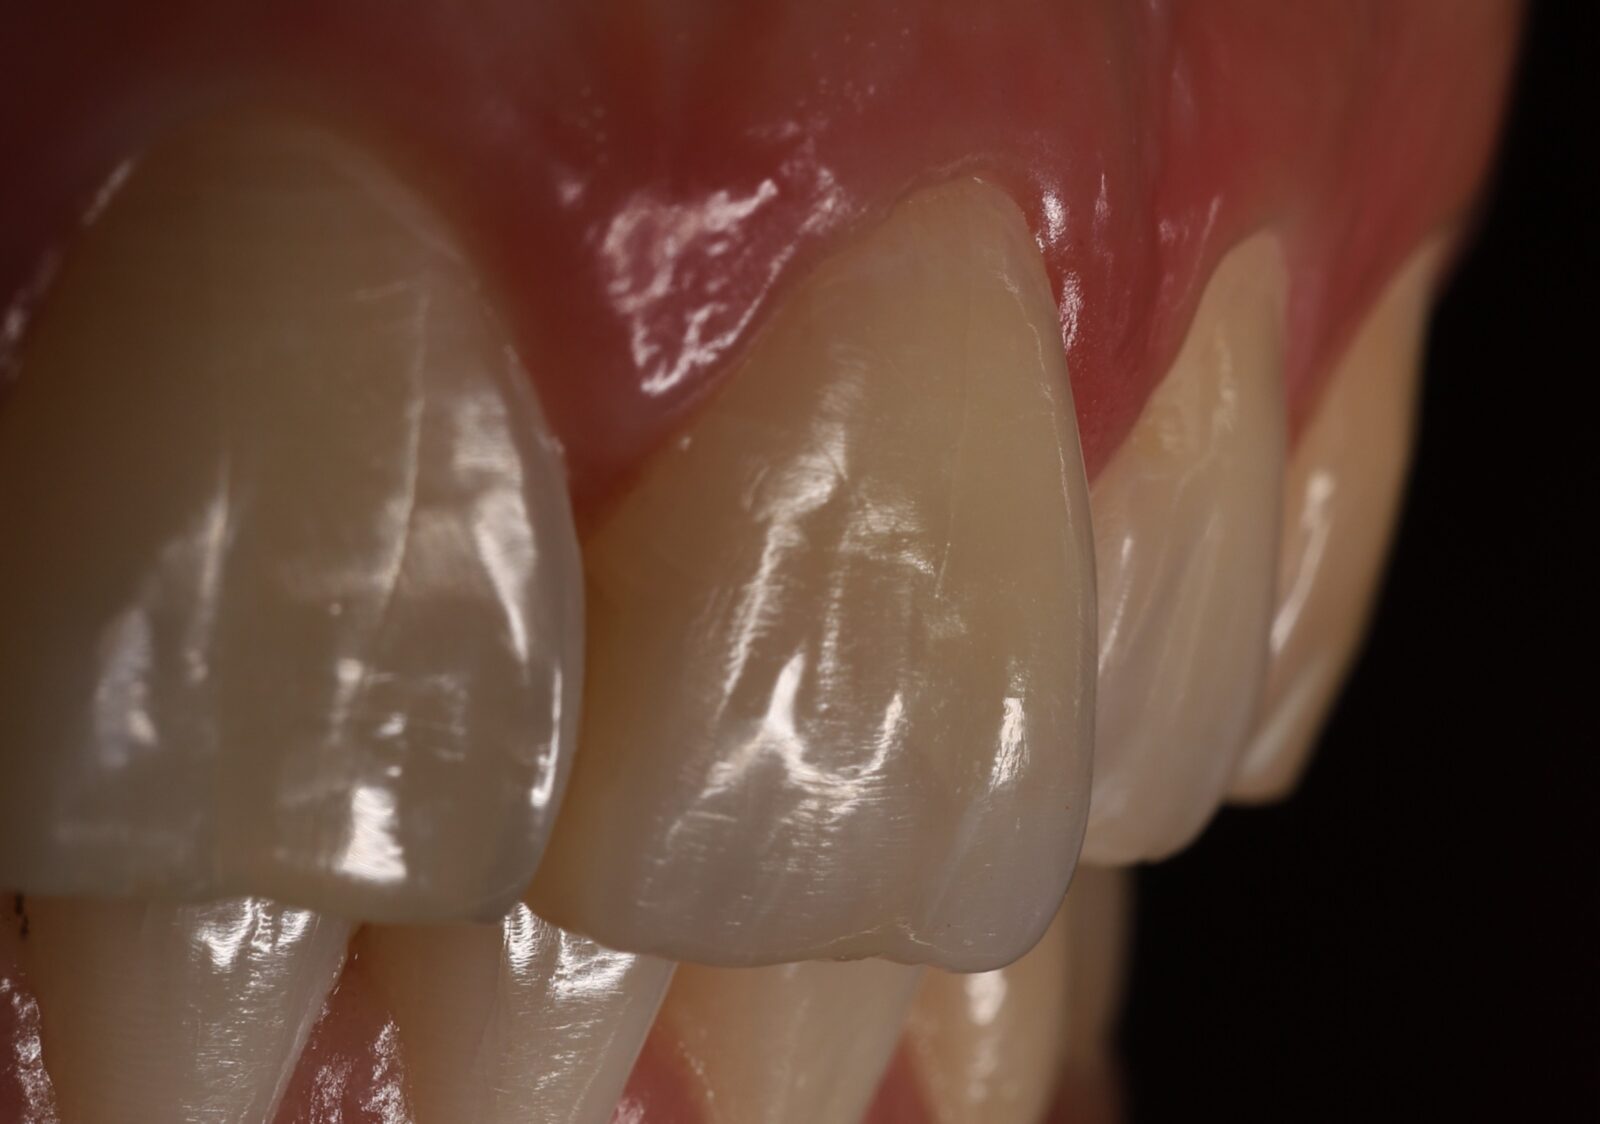

Внутриротовые фотографии 17.10.2022г